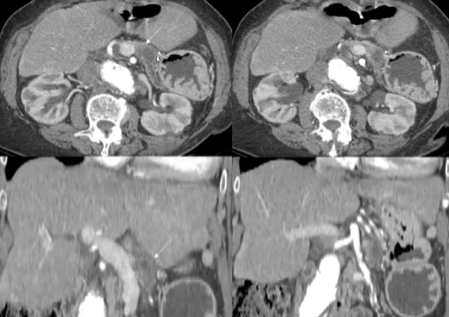

73岁,女,超声偶然发现胰体卵圆形病变,活检粘液腺癌。CT 2X3cm 胰腺病变,Wirsung 管扩张,没有远处转移。CEA 9.74,CA19-9 2066 U/ml

MDT,患者合并有缺血性心脏疾病,高血压,II型糖尿病,巨大腹壁切口疝和腹主动脉瘤。不适合外科治疗,建议IRE

with percutaneous approachIRE treatment with lower probe repositioning and 1 cm pull back.

经皮入路治疗,探针(19g,15mm),,3 probes (19 G with 15 mm exposition) 探头复位,后退1cm。

无围手术期并发症 No periprocedural complication noted

1年以后随访 ,肿瘤标志物 6.30ng/ml;CA19-9 129.9U/ml |

病变边缘清楚,不适合外科治疗